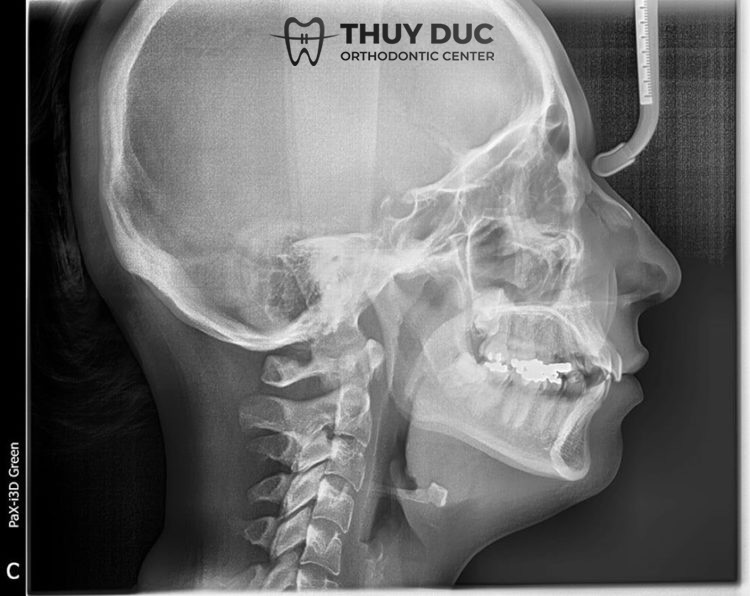

Xác định hô do răng hay hô do hàm là bước đầu tiên và việc quan trọng nhất trong quá trình điều trị hô. Để làm được điều này cần có sự thăm khám của bác sĩ Răng Hàm Mặt, khi đó bác sĩ sẽ thông qua hình ảnh chụp phim để phân tích tình trạng hô, tìm ra nguyên nhân và tác nhân gây hô ở mỗi bệnh nhân. Do đó, những mẹo hay việc quan sát bằng mắt thường qua góc nghiêng, đường cong chữ S được lan truyền nhiều trên Internet là chưa thực sự chính xác và thường không đúng với tất cả trường hợp.

- Chụp X-quang để xác định rõ cấu trúc xương hàm mặt, độ dày của xương. Đồng thời, các bác sĩ đánh dấu vị trí mạch máu, dây thần kinh để lên phương pháp điều trị phù hợp.